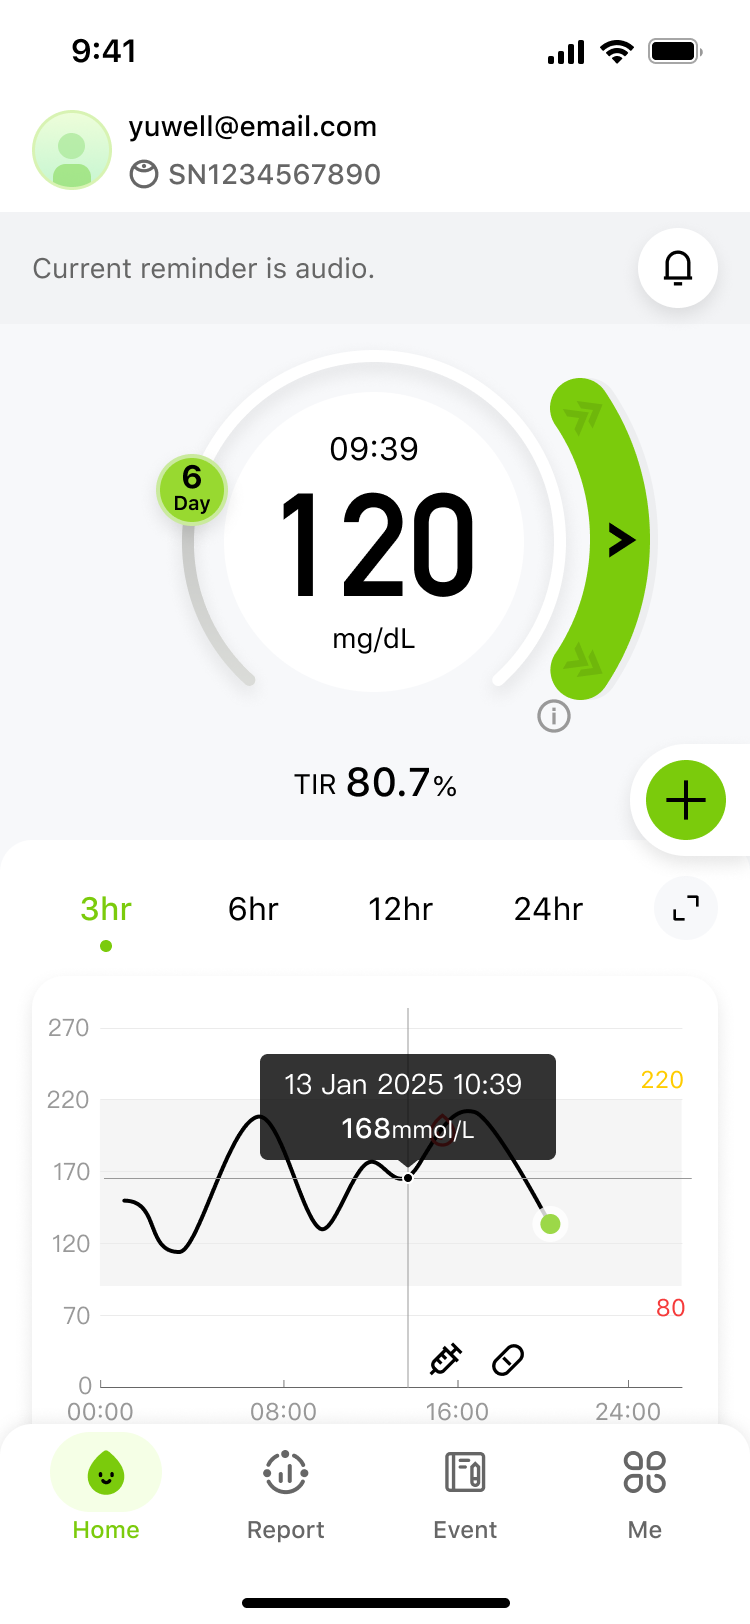

Turn your continuous glucose data into actionable insights. Unlock how your diet, exercise, and sleep personally affect you. Easily monitor your levels and generate professional reports anytime, anywhere. This is health management, simplified—putting you in control of your future.